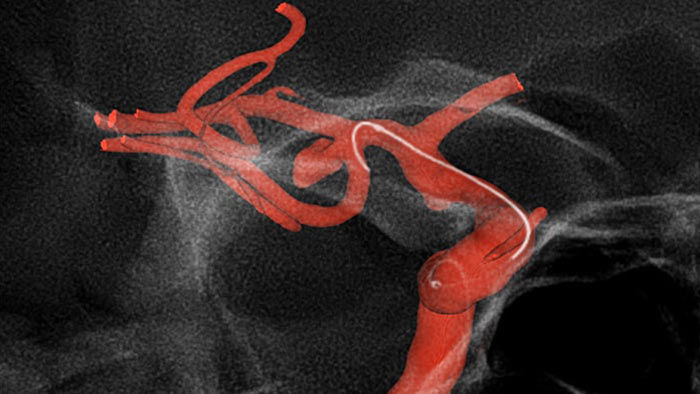

SmartCT Roadmapは、重なり合う血管を視覚化して、複雑な血管構造を通過する際のガイドワイヤおよびカテーテルの正確なナビゲーションをサポートします。ガントリ、テーブル、および患者の体動をリアルタイムで補正し、高精度を実現します。